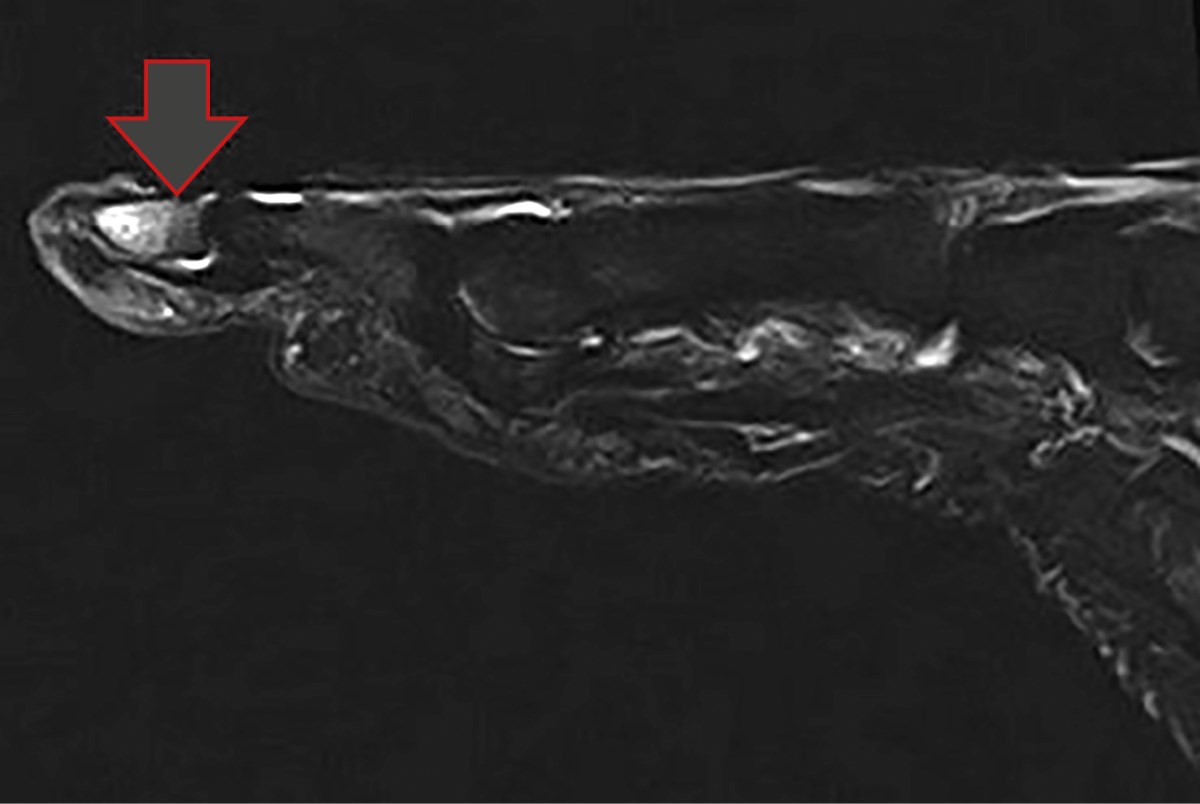

Магнитно-резонансная томография правой стопы выявила трабекулярный отек костного мозга дистальной фаланги первого пальца (рис. 3). Этот отек может свидетельствовать о воспалительном процессе или процессе асептического некроза, что типично для пациентов с СДС, у которых часто наблюдаются нарушения микроциркуляции.

Рисунок 3. Магнитно-резонансная томография правой стопы. Трабекулярный отек костного мозга дистальной фаланги первого пальца.